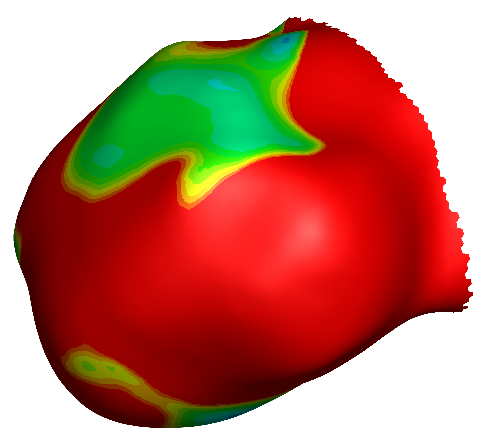

壁面剪切应力

振荡剪切因子

相对滞留时间

WSS:壁面剪应力,表示血流作用于血管壁而产生的切向作用力。颜⾊越红,血流作用于血管内壁的摩擦力越大。

OSI:振荡剪切因子,表示WSS方向变化在心动周期中对血管壁的作用。颜⾊越红,WSS方向变化越大。

RRT:相对滞留时间,表示血流在血管壁附近的停滞时间。颜⾊越红,血流停滞时间越长。